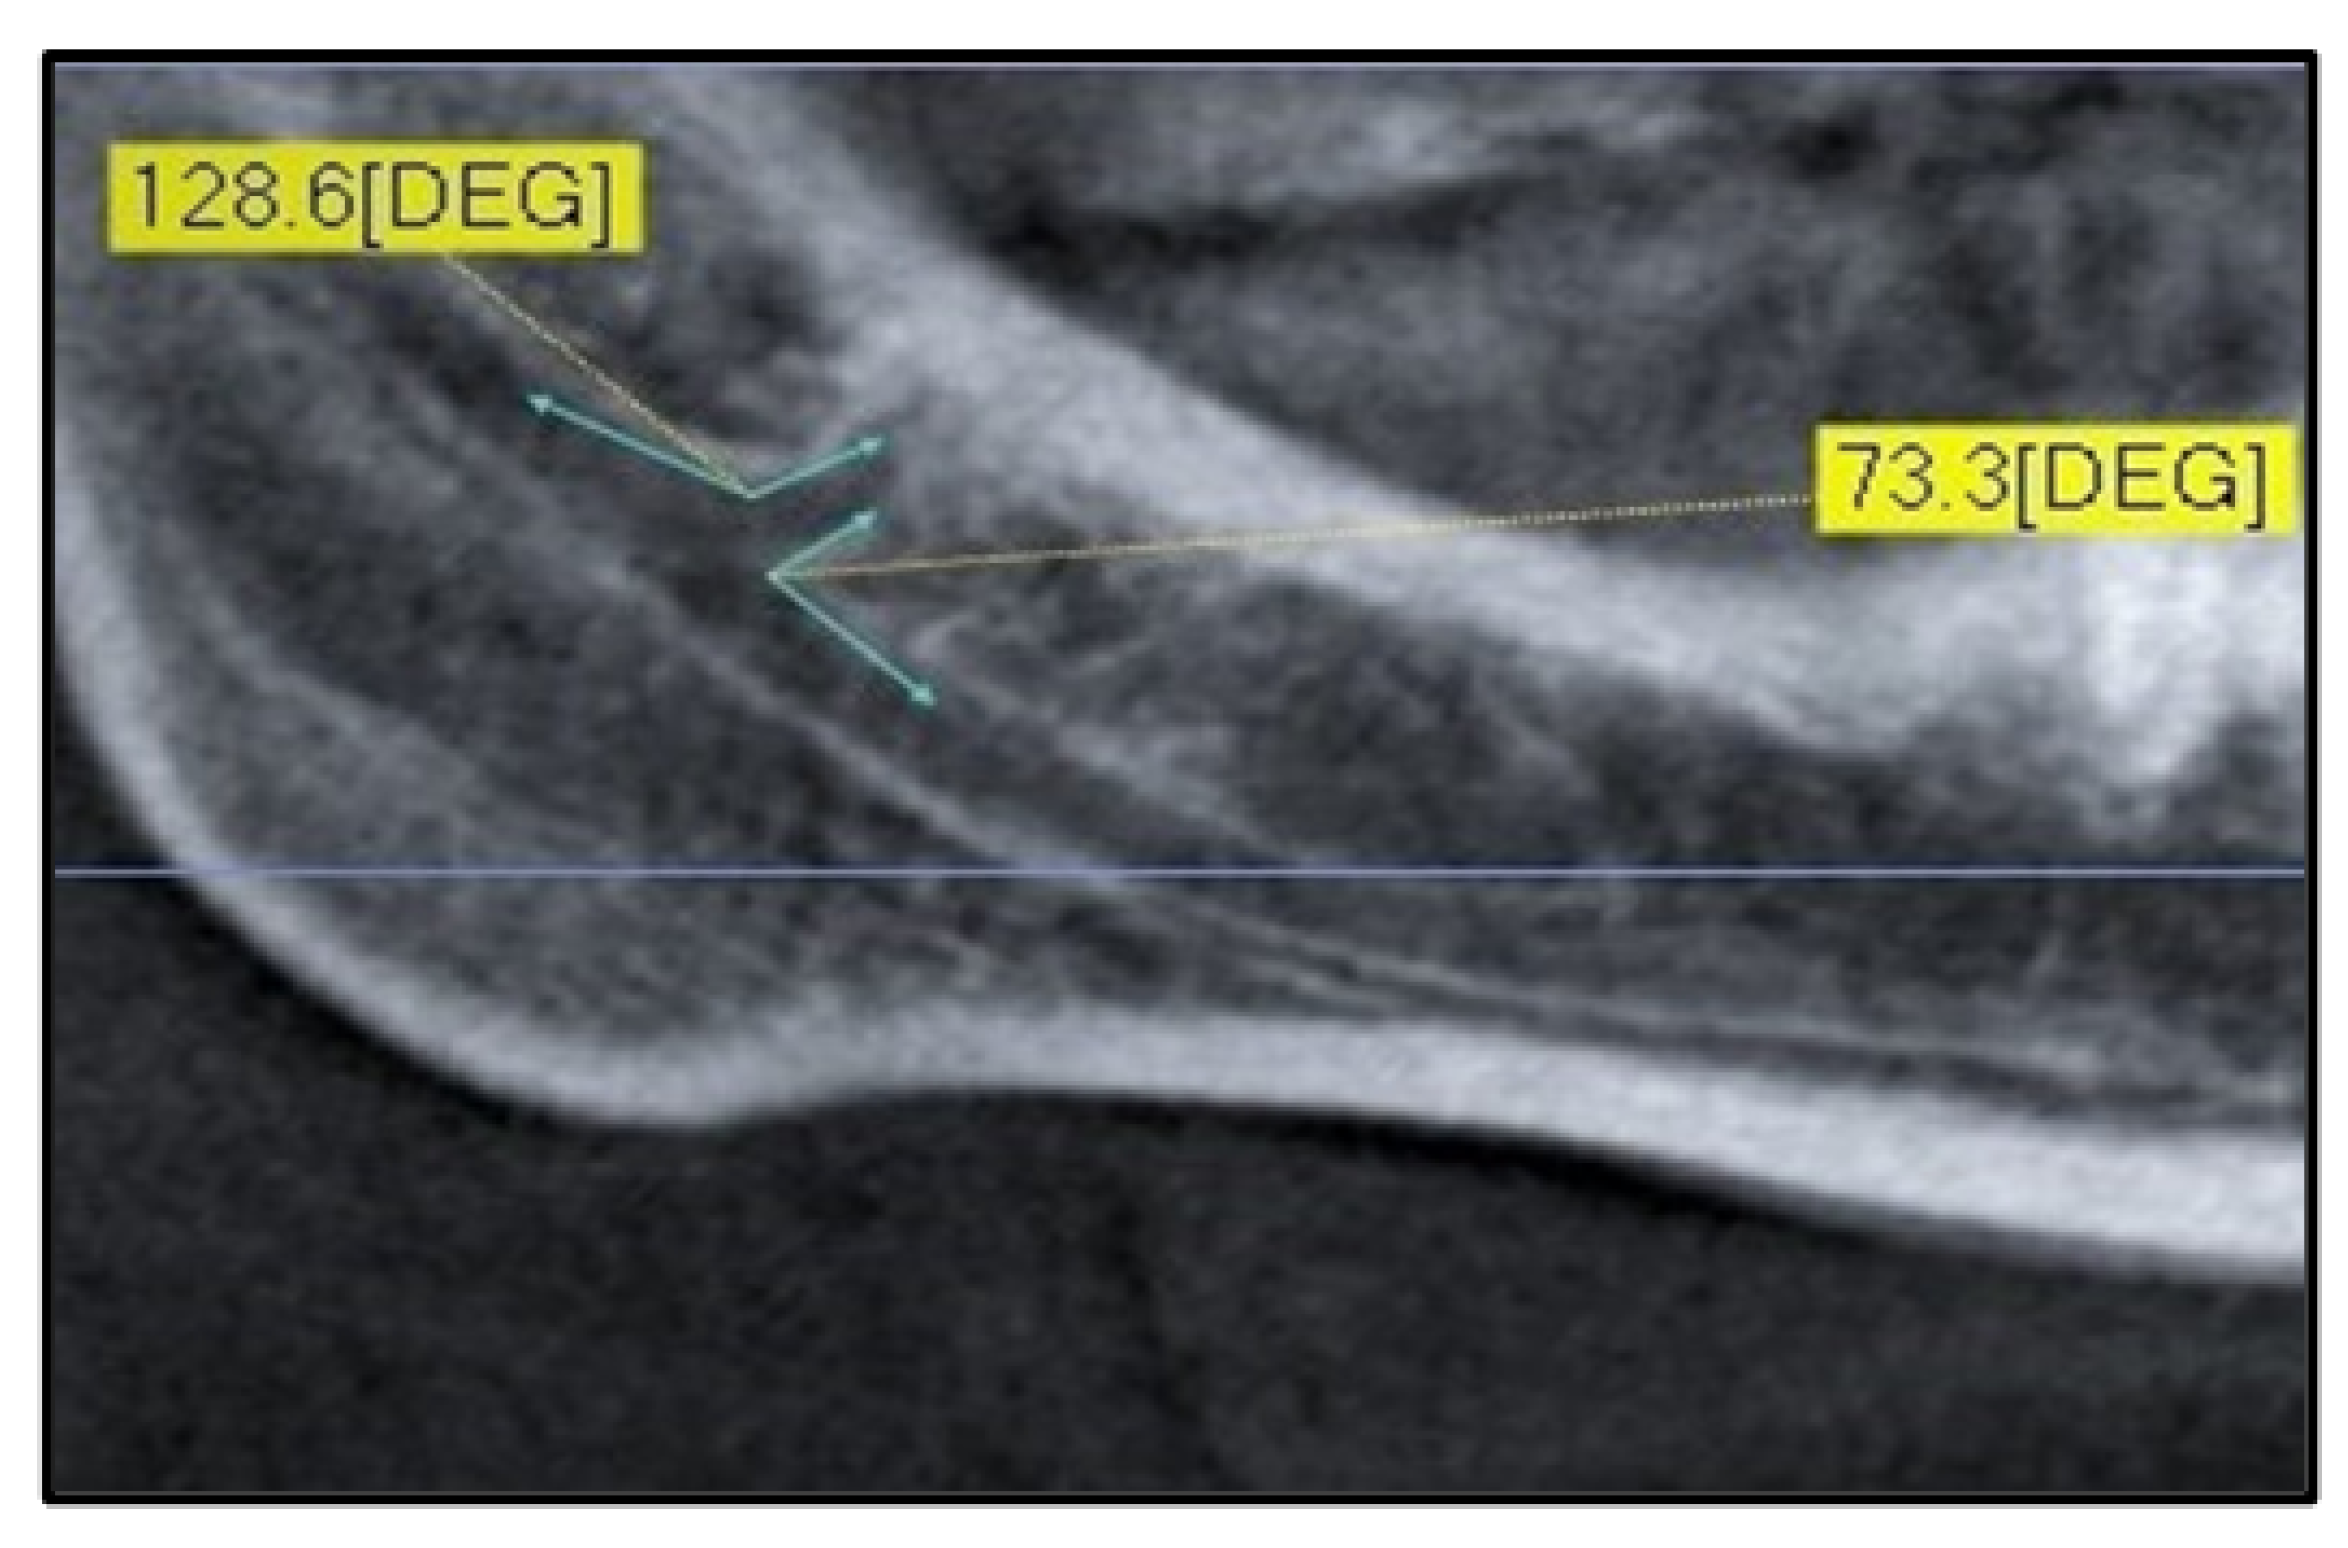

| Ang. sup. right (°) | 92 | 22.50 | 162.20 | 123.70 | 24.30 |

| Ang. inf. right (°) | 92 | 11.90 | 130.40 | 56.02 | 23.55 |

| Ang. sup. left (°) | 81 | 35.60 | 167.00 | 118.05 | 29.00 |

| Ang. inf. left (°) | 81 | 8.70 | 154.30 | 62.75 | 32.45 |